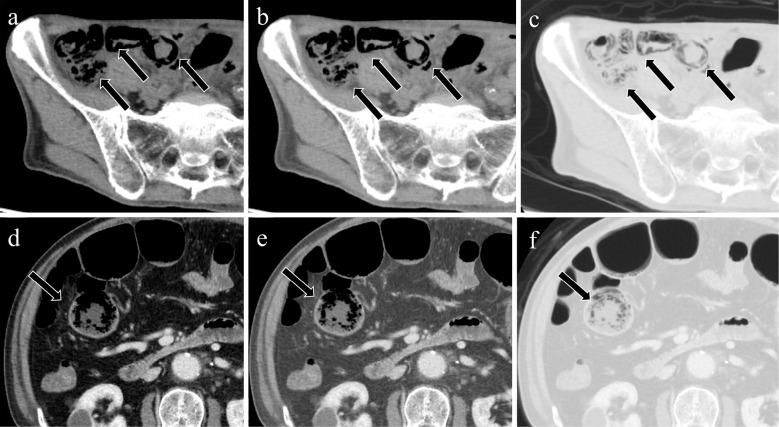

Acute mesenteric ischemia is a life-threatening condition. A comprehensive approach involving a multidisciplinary team to review patient background, clinical history, physical examination, laboratory data, and imaging examination for respective diagnosis of superior mesenteric arterial occlusion, nonocclusive mesenteric ischemia, and superior mesenteric venous occlusion is essential. The most important imaging modality is computed tomography, which is used for diagnosis and for directing therapeutic strategy (e.g., endovascular revascularization, surgical bowel resection, or conservative management). Computed tomography image findings can support triaging of irreversible transmural bowel necrosis compared with reversible ischemic change with reperfusion. In this review article, the computed tomography imaging findings specifically associated with the pathophysiology of superior mesenteric arterial occlusion, nonocclusive mesenteric ischemia, and superior mesenteric venous occlusion are reviewed.

急性肠系膜缺血是一种危及生命的疾病。采用多学科团队的综合方法来审查患者背景、临床病史、体格检查、实验室数据以及影像学检查,以分别诊断肠系膜上动脉闭塞、非闭塞性肠系膜缺血和肠系膜上静脉闭塞至关重要。最重要的影像学检查方法是计算机断层扫描,它用于诊断并指导治疗策略(如血管内血运重建、手术肠切除或保守治疗)。计算机断层扫描图像结果有助于区分不可逆的透壁性肠坏死与可通过再灌注逆转的缺血性改变。在这篇综述文章中,将对与肠系膜上动脉闭塞、非闭塞性肠系膜缺血和肠系膜上静脉闭塞的病理生理学具体相关的计算机断层扫描影像学结果进行综述。